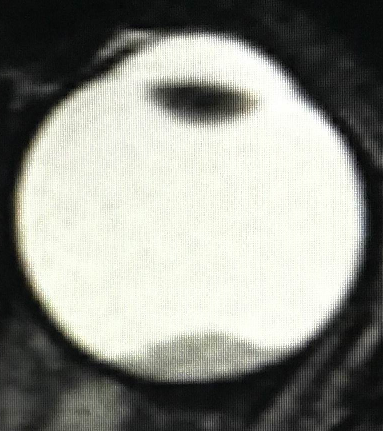

МРТ головного мозга и орбит

Магнитно-резонансная томография дает возможность в деталях увидеть распространение процесса за пределы глазного яблока и точно определить стадию болезни. Такое исследование нужно проводить всем пациентам, у которых ретинобластома диагностирована впервые. Контраст при МРТ повышает информативность.

image004.pngРис. 2. Визуализация ретинобластомы с помощью МРТ. Клиническая группа В